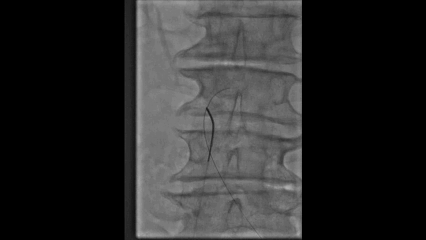

超声引导下穿刺左侧腘静脉置入鞘管

行左下肢静脉及髂静脉造影

尝试通过腘静脉、股浅静脉、髂股段静脉病变

发现股浅静脉近端闭塞,通过侧支与股深静脉沟通

髂静脉闭塞,盆腔侧支静脉形成